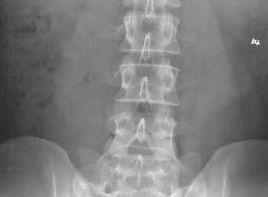

除腰部有一般症狀外,診斷主要依據X線檢查確診。